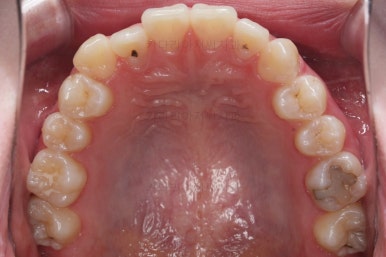

각설하고 위의 사진들은 부산치아교정잘하는곳 키다리아저씨치과에서 처음 내원하셨을 때의 사진입니다.

그리고 오른쪽 위 송곳니가 덧니처럼 볼록하여 웃거나 말할 때 자신감 있게 입을 벌리지 못하고 있었어요.

아랫니는 크게 심하지 않았고 윗니 앞니쪽에 치열이 삐뚤한 것을 볼 수 있어요.

그리고 위아랫니의 중앙선도 어긋나 있는 것으로 봐서 왼쪽과 오른쪽의 교합 자체도 다르고 문제가 있음을 알 수 있었어요.